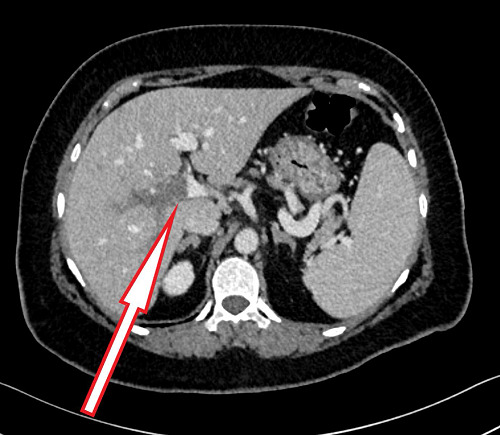

背景:肥胖和2型糖尿病(T2DM)是对全球医疗保健产生重大影响的现代流行病。胰高血糖素样肽-1受体激动剂(GLP1-RA) semaglutide是治疗tbl2DM和肥胖的一种新方法,但可能与静脉血栓栓塞的风险增加有关。病例介绍:本病例报告描述了一位59岁的tbl2DM女性患者,她接受了西马鲁肽来控制血糖水平,并经历了体重减轻的额外好处。在启动GLP1-RA的6个月内,患者出现腰痛,伴有恶心和口腔摄入不良。她没有已知的静脉血栓栓塞或血栓形成的危险因素,家族中也没有重大疾病史。她的体格检查未见明显发现。仅见轻度白细胞增多和嗜中性粒细胞增多。她接受了腹部计算机断层扫描,发现肝内门静脉血栓形成,但没有肝硬化或腹部恶性肿瘤的证据。口服抗凝药(利伐沙班)后症状得到改善。除Janus激酶2突变可能增加血栓形成的风险外,血栓检查结果为遗传性或获得性血栓形成阴性。结论:由于对减肥药的需求日益增长,GLP1-RA的使用正在增加。因此,医生在开始GLP1-RA治疗前更好地了解血栓形成的可能风险是很重要的。

Background: Obesity and type 2 diabetes mellitus (T2DM) are modern-day pandemics that have a significant impact on global healthcare. The glucagon-like peptide-1 receptor agonist (GLP1-RA) semaglutide is a novel treatment for both tbl2DM and obesity, but can be associated with an increased risk of venous thromboembolism. Case presentation: This case report describes a 59-year-old woman with tbl2DM who received semaglutide to manage glycemic levels, and also experienced the additional benefit of weight reduction. Within six months of initiating GLP1-RA, the patient experienced low back pain associated with nausea and poor oral intake. She had no known risk factors for venous thromboembolism or thrombophilia and had no history of significant illness in her family. Her physical examination revealed no significant findings. Only mild leukocytosis and neutrophilia were noted. She underwent an abdominal computed tomography scan, which revealed intrahepatic portal vein thrombosis without evidence of liver cirrhosis or abdominal malignancy. Her symptoms improved with oral anticoagulation (rivaroxaban). The result of thrombophilia examination was negative for inherited or acquired thrombophilia, except for a Janus kinase 2 mutation, which may increase the risk of thrombosis. Conclusions: The use of GLP1-RA is increasing due to the growing desire for weight loss medications. Therefore, it is important that physicians better understand the possible risks of thrombosis before initiating GLP1-RA treatment.